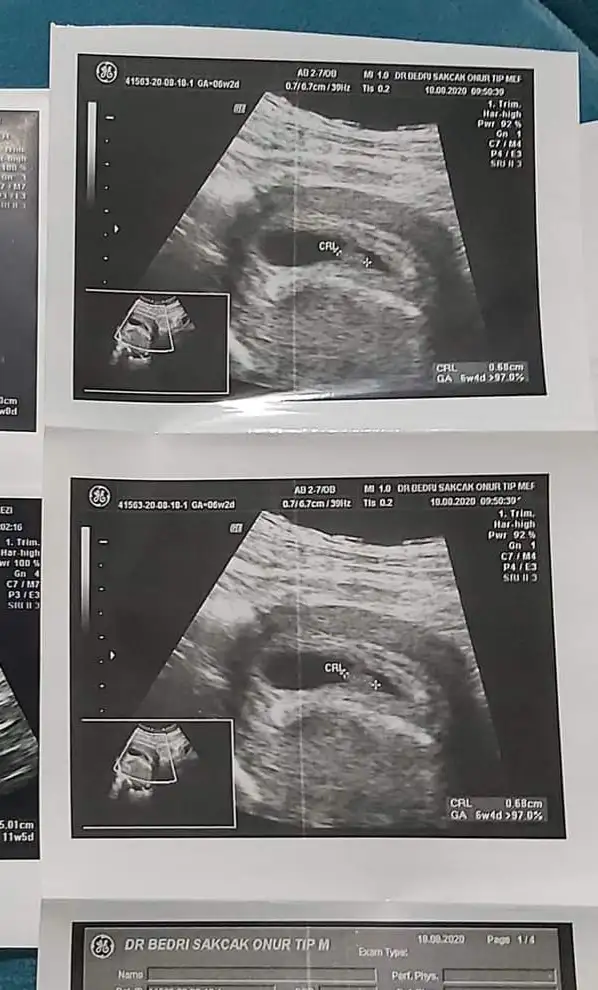

6-7 hafta arası varsa yorumlayabilirim ama uzman değilim öyle eğlencesineEki Görüntüle 2789978 lutfen yorum yaparmisiniz kizmi erkekmi

Sanırım kız gibi geldi banaMerhaba benim bebişin cinsiyetinide tahmin edebilir misiniz?Üzerinde haftalar yazıyor . 6 haftalık vajinadan 7 haftalık karından simdiden teşekkür ederim

Karından sanırım eğer öyleyse erkek gibi geldi ama bebeğin yerinden dolayı tahmin ediyorum bazı arkadaşlar plesantaya göre yapıyor ben onu bilmiyorumBu kız kardeşimin bebeği cinsiyeti belli oldu sizce nedir